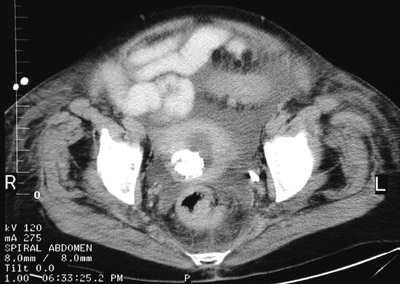

| There is a bright rounded mass in the uterus seen in this pelvic CT scan that represents a calcified leiomyoma. Leiomyomas tend to involute following menopause and become more fibrous, with some exhibiting dystrophic calcification. Note the small fluid collection in the endometrial cavity that occurs in some older women with cervical stenosis. |